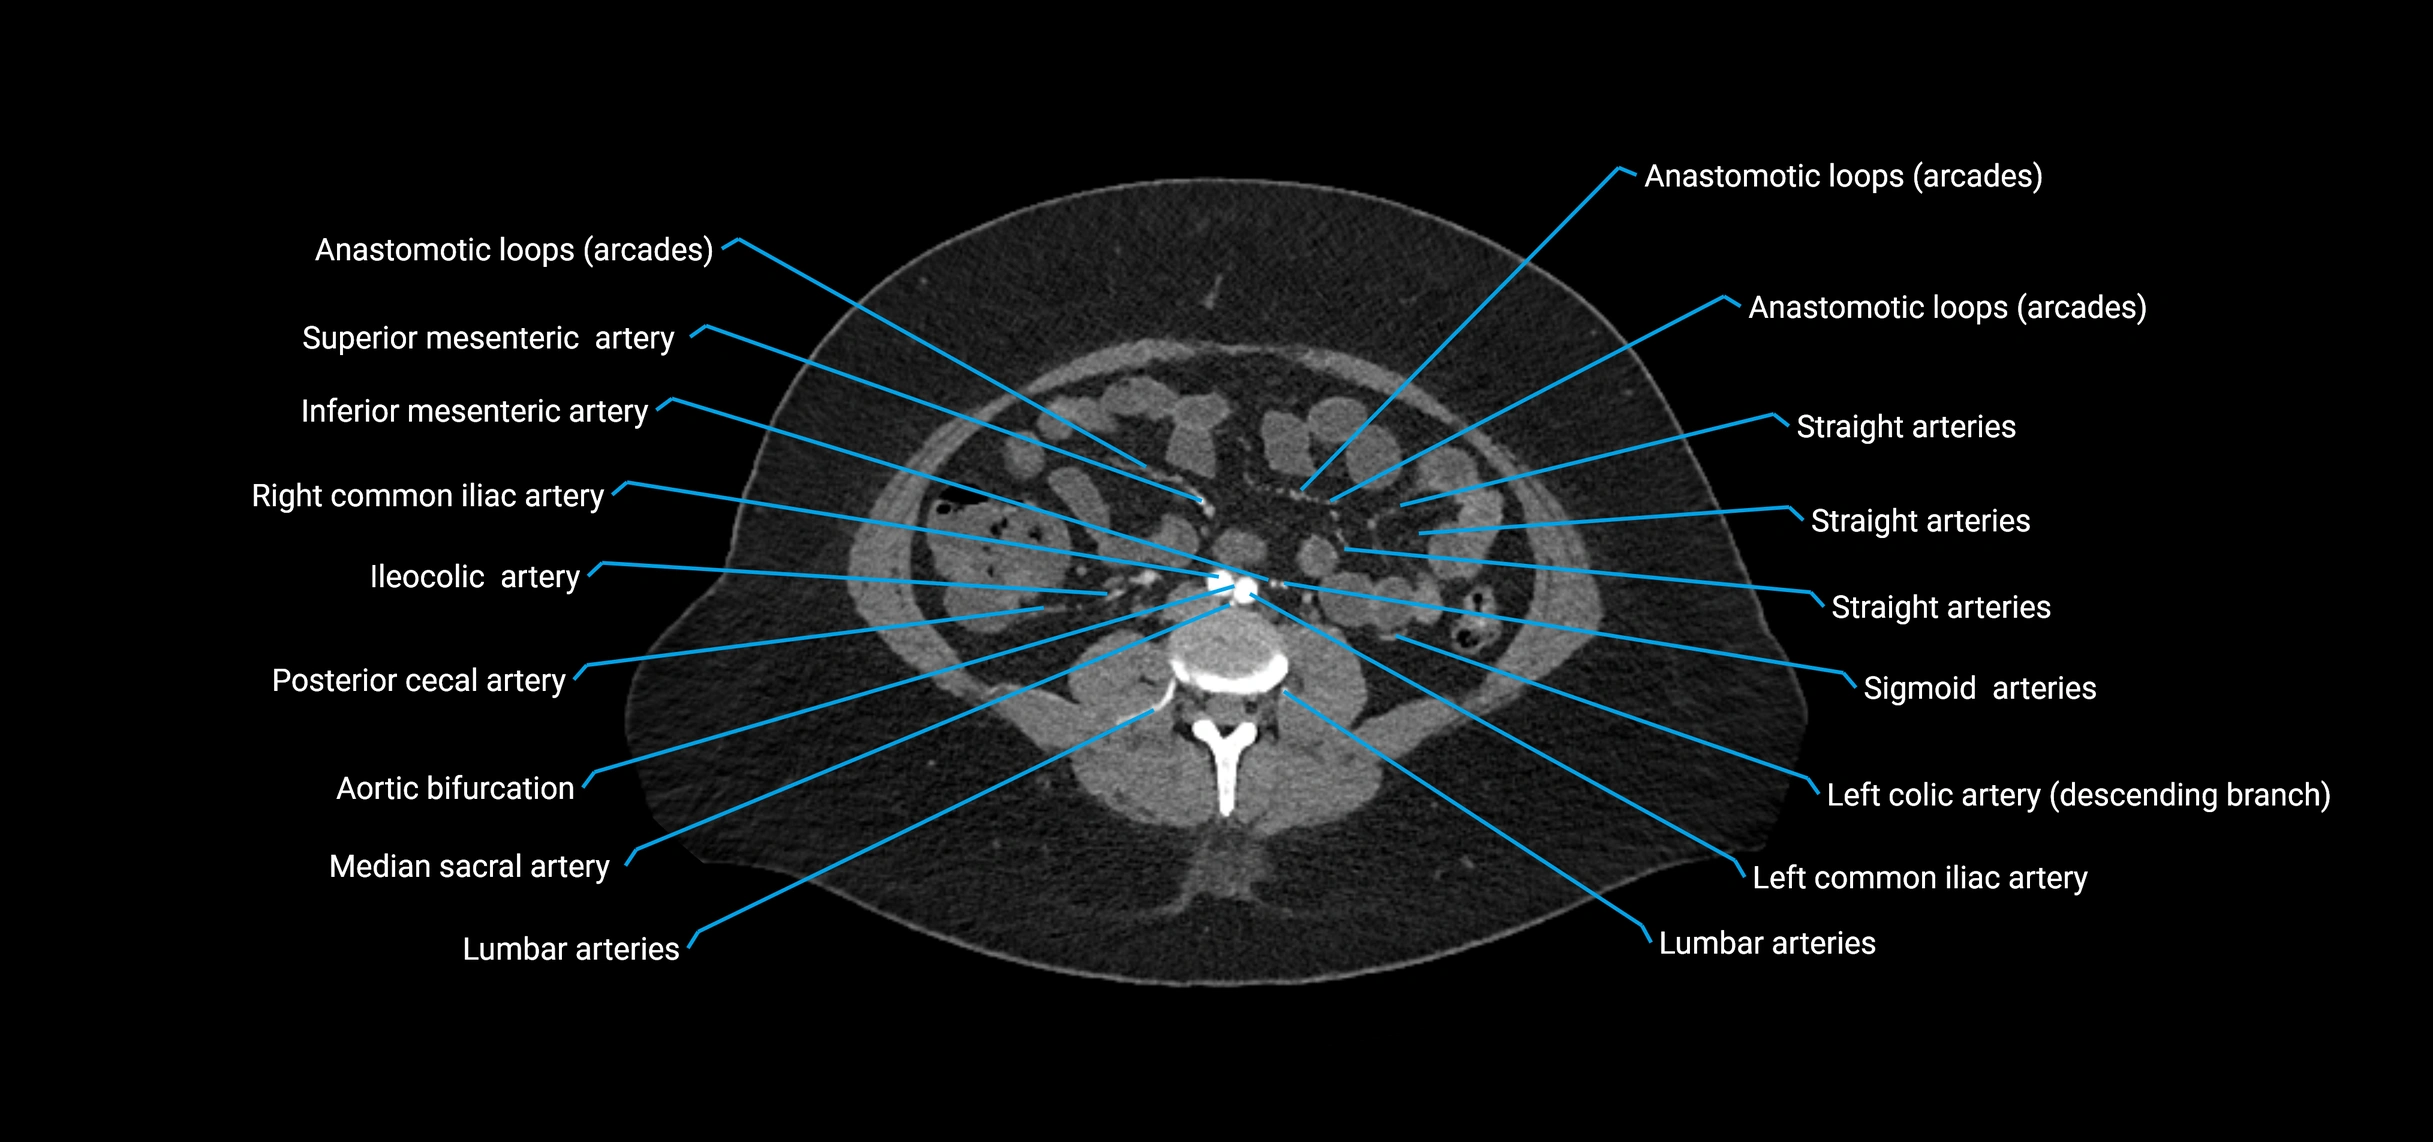

Contrast-enhanced CT (CTA):

• Gold standard for abdominal aortic imaging

• Provides excellent detail of lumen, wall, aneurysm, thrombus, and branch vessels

• Multiplanar and 3D reconstructions help in aneurysm measurement, stent graft planning, and dissection evaluation

• Detects acute rupture, traumatic injury, or occlusion with high sensitivity